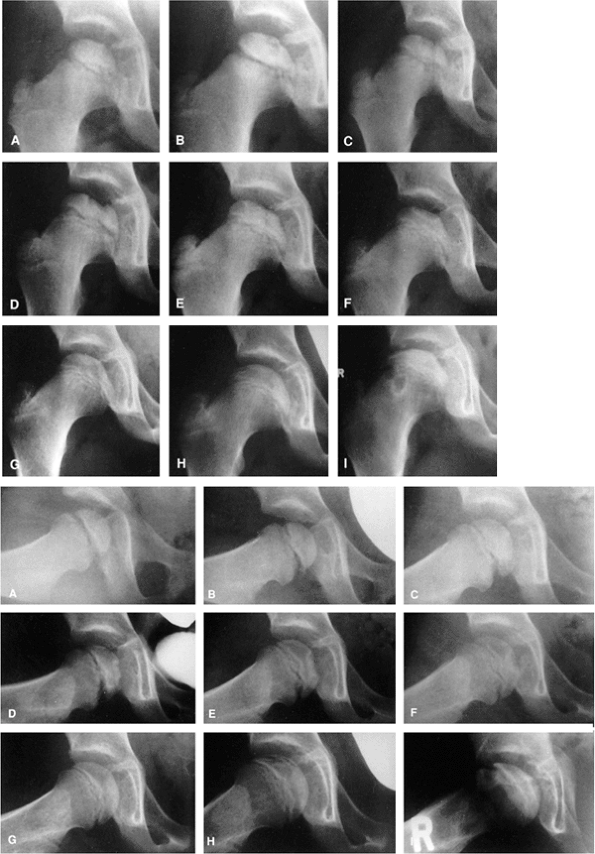

A girl, 4 years and 8 months of age, was treated for left hip Perthes disease (late fragmentation phase) beginning in January 1983. Anteroposterior (right, A–I) and Lauenstein (see pg. 1044, A–I) views of the right hip at different stages, January 1983 to December 1987. A: View of the right hip at the time of initial presentation with no signs of involvement (January 1983). B: Early involvement, patient still asymptomatic (September 1983). C–F: Progressive healing of the right femoral epiphysis at May 1984 (C), August 1984 (D), May 1985 (E), and November 1985 (F). G: Femoral head was completely healed by December 1986. H: Recurrent changes in the density of the femoral head and a subchondral fracture that involves less than 50% of the head (Catterall group 2) was seen in June 1987. I: Complete involvement of the ossific nucleus (Catterall group 4) with diffuse metaphyseal reaction and cysts in December 1987. (From Martinez AG, Weinstein SL. Recurrent Legg-Calvé-Perthes’ disease: case report and review of the literature. J Bone Joint Surg Am 1991;73:1081.) |